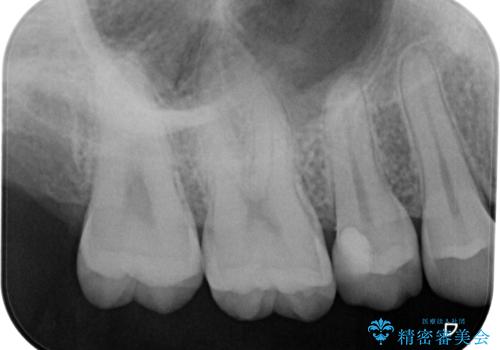

食べ物が頻繁に詰まるとのことで、レントゲンで確認したところ、歯間部に齲蝕が認められました。

ぱっと見ではわかりずらい齲蝕ですが、レントゲン写真でははっきりと確認することができます。

齲蝕がより進行すると神経の処置が必要になってしまう可能性があるため、早期発見・治療のための定期健診の重要性がわかります。